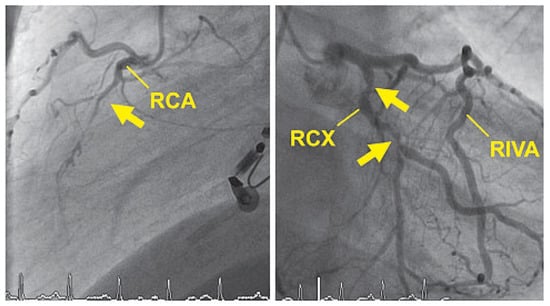

Up to ten percent of acute coronary syndromes occur during or shortly after physical exercise. In fact, physical exertion of more than 4 METs transiently increases the risk for myocardial infarction which remains elevated until an hour afterwards. Th...